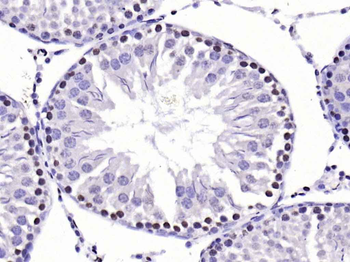

CDKN1A Antibody

Catalog Number: orb682382

| Description | CDKN1A Antibody |

| Target | CDKN1A |

| UniProt ID | P38936 |